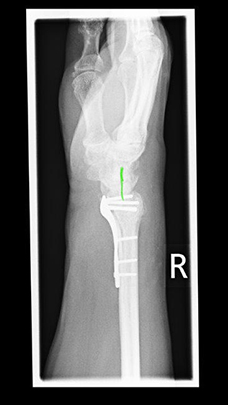

Radiusfraktur vor Korrekturoperation mit anhaltende beugeseitige Verschiebung der Handwurzel

Radiusfraktur vor Korrekturoperation: Die beugeseitige Knochenlippe ist über die liegende Platte hinweg verschoben.